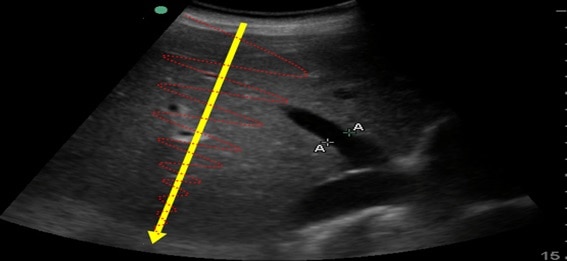

En la imagen siguiente, podemos distinguir el hígado (estrella azul, de una densidad determinada) de la vesícula (estrella verde, de un contenido líquido, de densidad menor) de la litiasis biliar (estrella roja, formada por calcio, de una densidad mucho mayor a las anteriores) porque entre cada una de estas estructuras se forma una interfase, al tener densidades (y por tanto impedancias) distintas.

En la imagen siguiente, se puede apreciar el fémur de un paciente. El ultrasonido llega hasta la interfase del hueso (muy denso) con el tejido circundante (muy poco denso) y se refleja con una intensidad alta (y por eso se muestra más “blanco” en la pantalla, como luego veremos).

Sin embargo, si atraviesa una interfase menos definida, en la que las densidades son similares, se dispersará en muchas direcciones diferentes, produciendo un eco de baja intensidad (que se representarán más “grises” en la pantalla), como ocurre al atravesar el parénquima hepático, donde las interfases son de densidad muy similar.